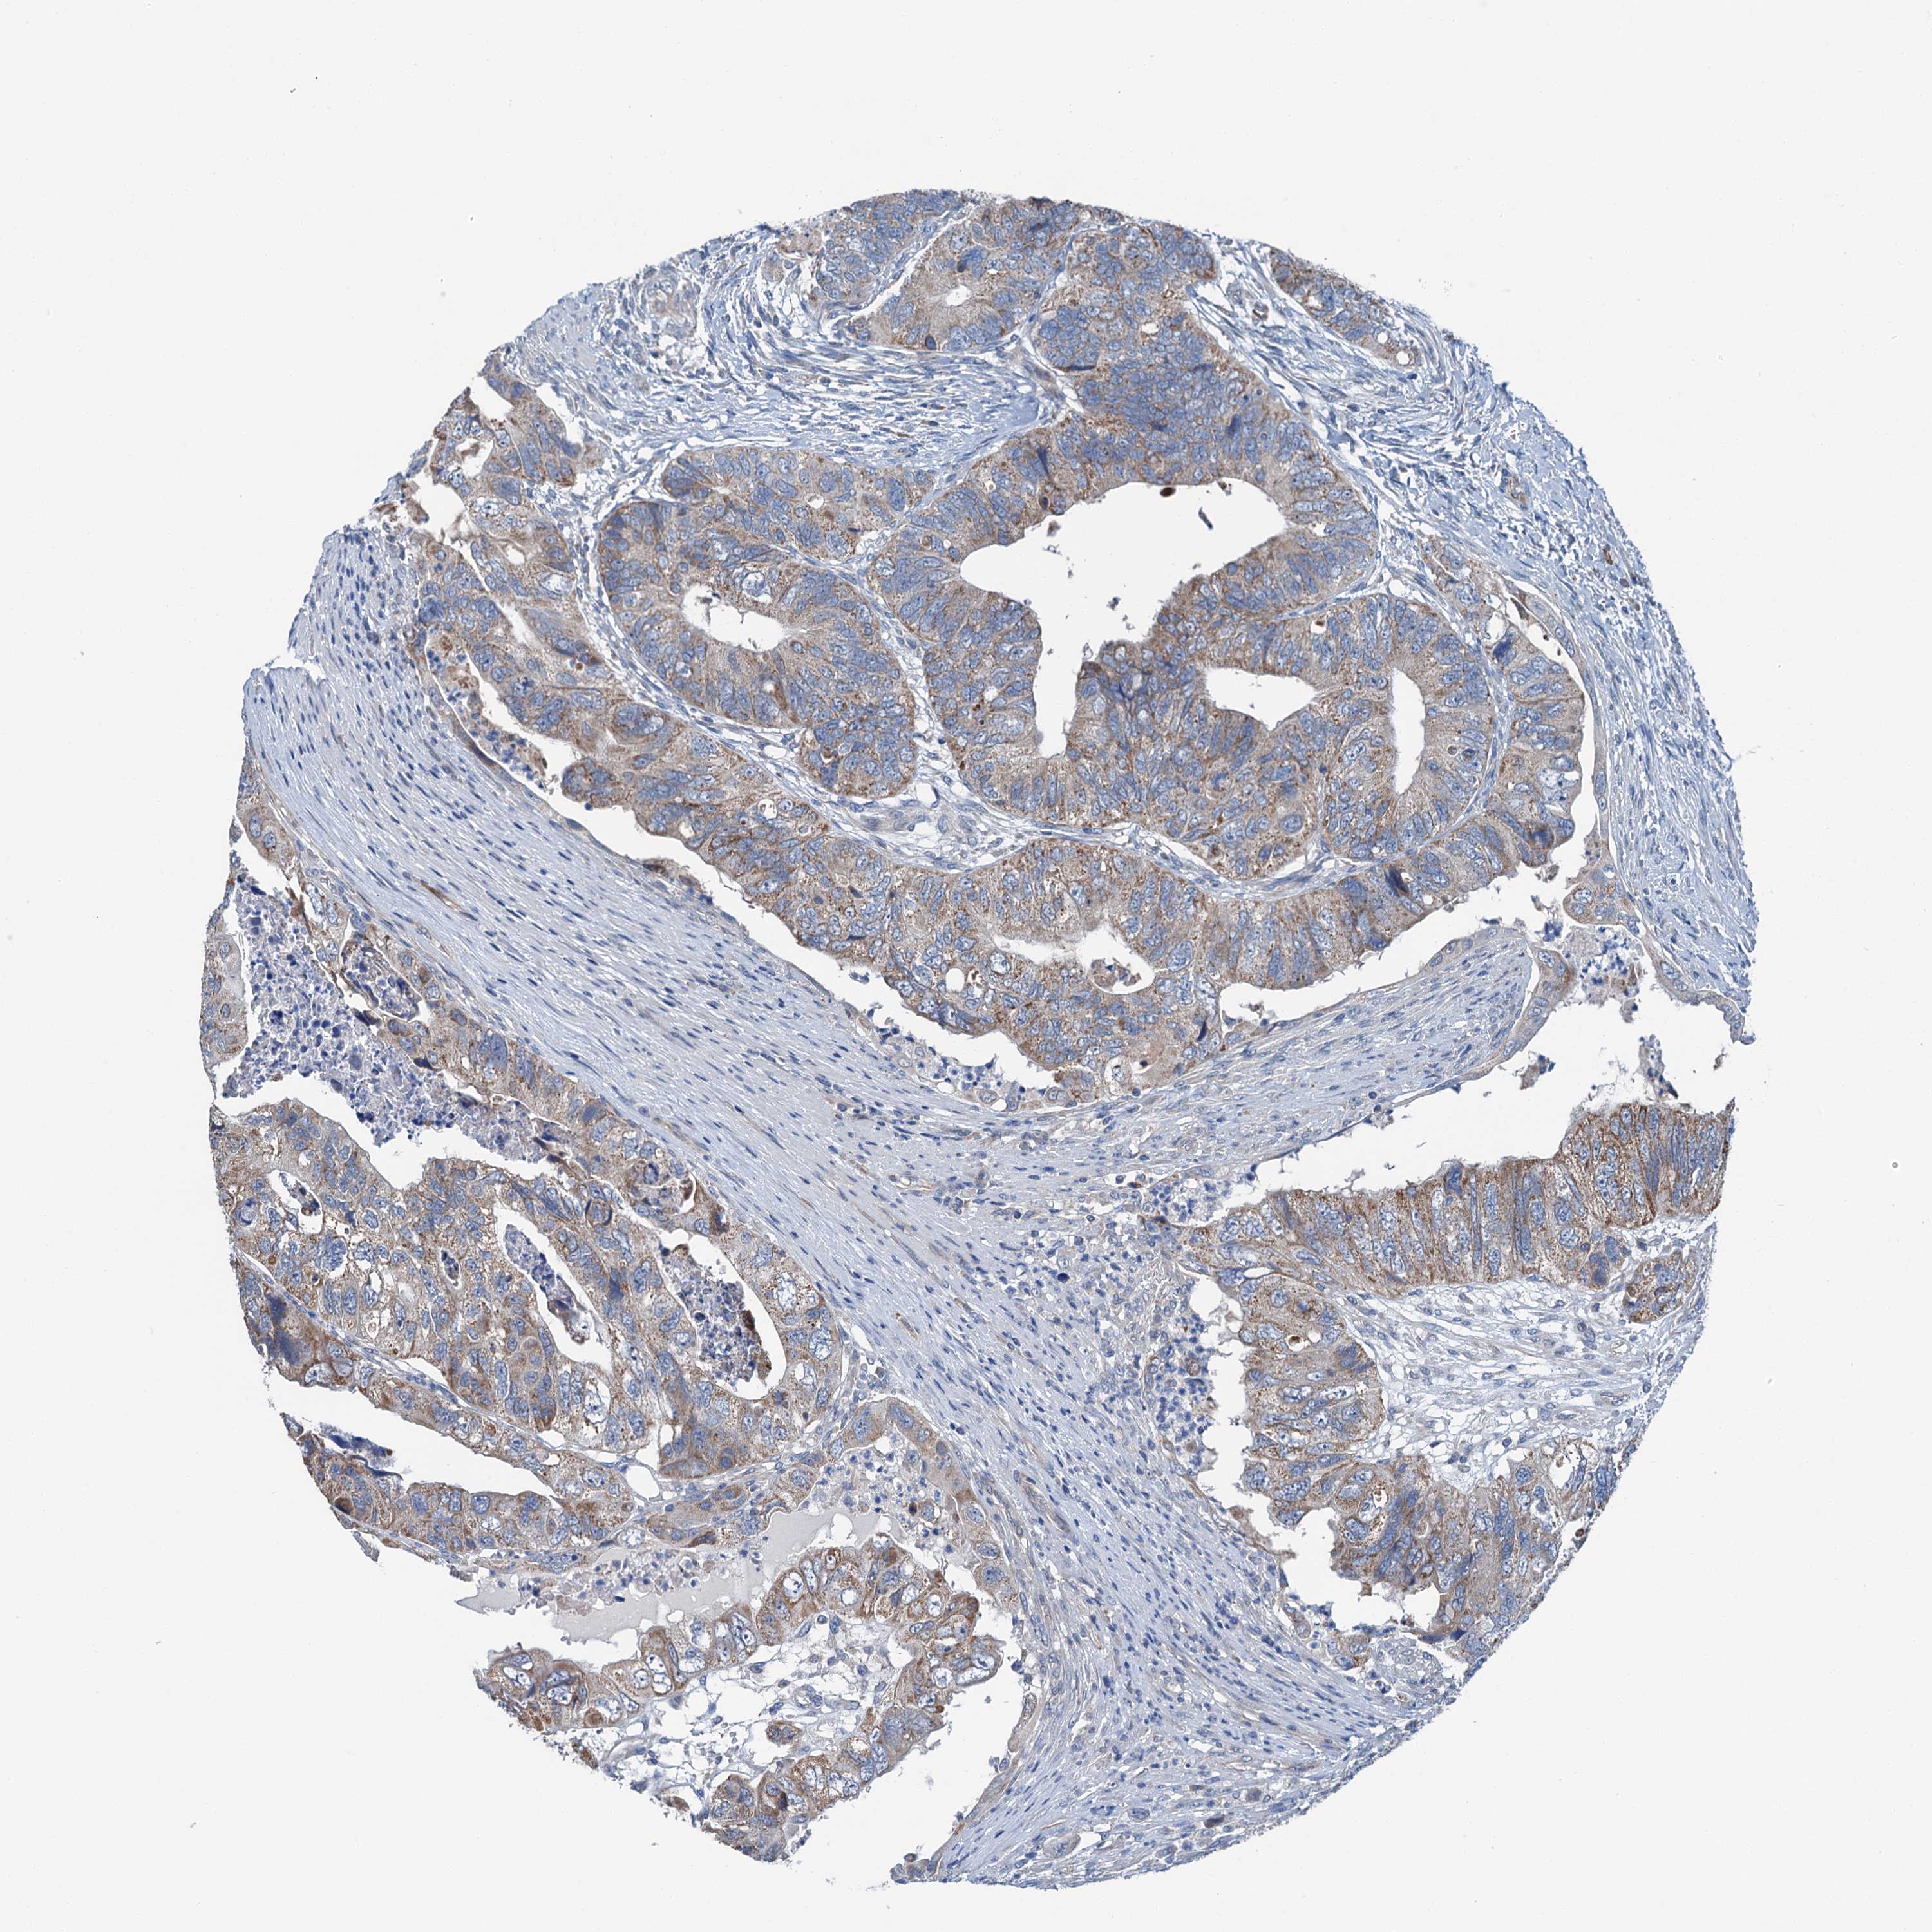

CANCER COLORECTAL CANCER Show tissue menu

Colorectal cancer

Human cancer

Colon adenocarcinoma